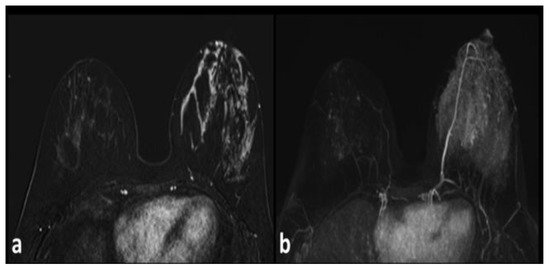

Unilateral Lactation